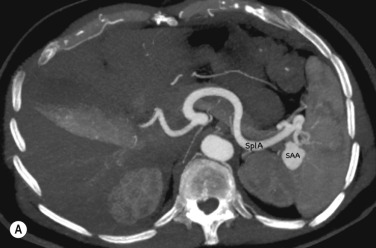

Visceral aneurysms at all other locations can also be diagnosed with CTA and MRA ( Fig. 77.2 ).

Fig. 77.2, Patient with incidental splenic artery aneurysm (SAA) demonstrated on computed tomography abdomen performed for lower abdominal pain. (A) Axial multiplanar reformat (MPR): note avidly enhancing 3-cm SAA at the splenic hilum (SplA) . (B) Coronal oblique MPR demonstrates the SAA. SMA , Superior mesenteric artery; SplA , splenic artery.